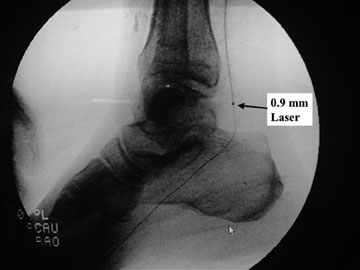

The 0.9 excimer laser probe, which has been available for several years, allows pedal atherectomy and revascularization. The new MiniHawk plaque excisional device (ev3) is now less than 2 mm in diameter and can infiltrate into pedal vessels. The recently available Diamondback 360 orbital atherectomy device (Cardiovascular Systems) also has a very low profile.Vascular interventionalists can utilize this device in infrapopliteal and pedal vessels with this design being particularly helpful in those highly calcified vessels that we see in diabetic and dialysis patients.